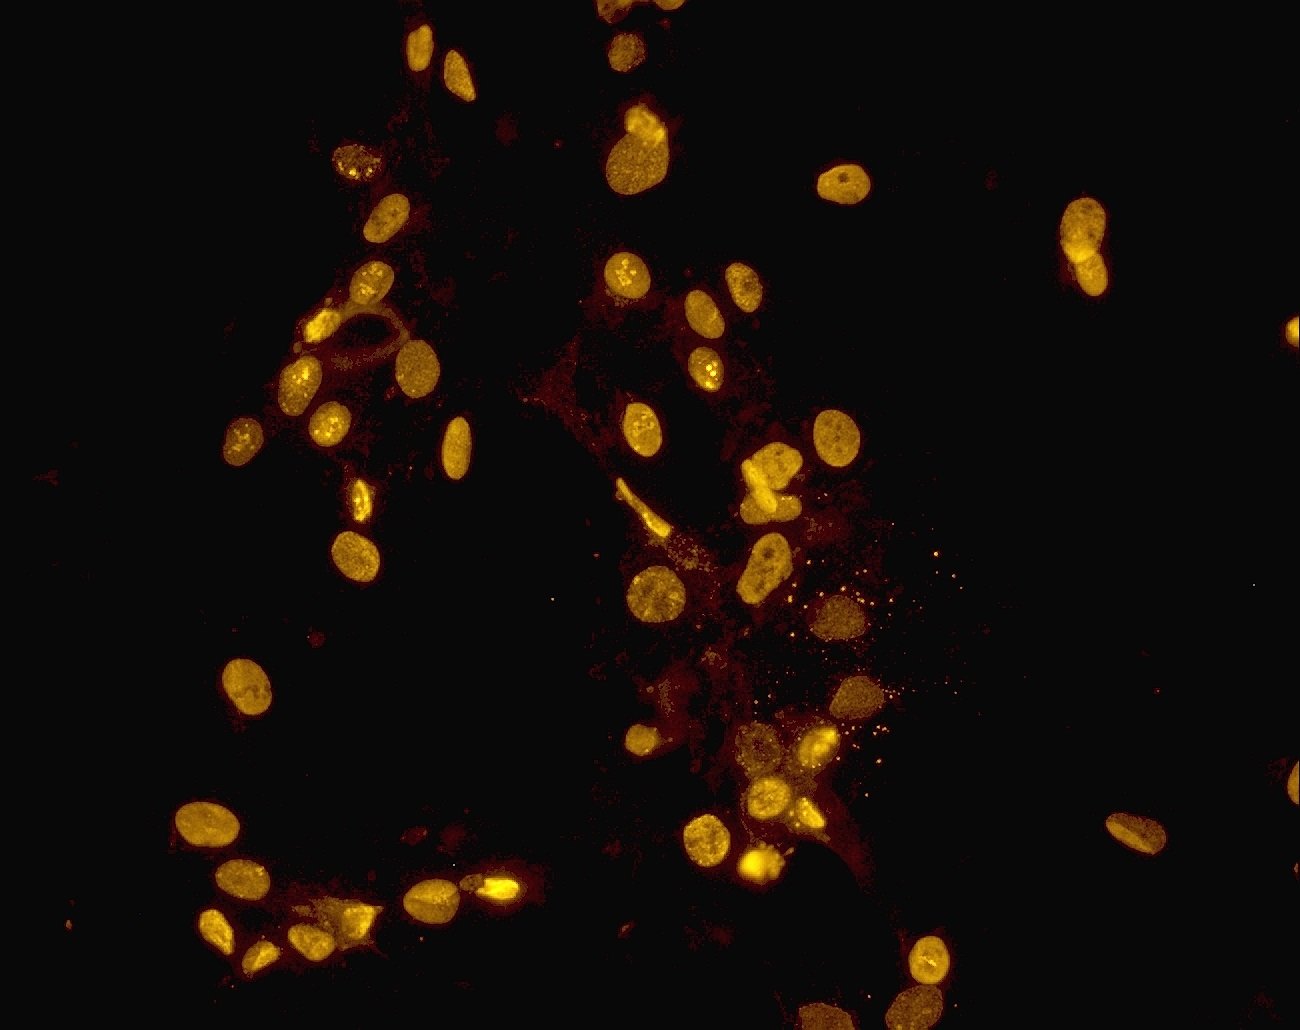

PICTUREEducation and Training Core